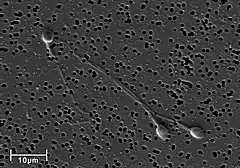

A human sperm cell consists of a flat, disc shaped head 5.1 µm by 3.1 µm and a tail known as a flagellum 50 µm long.[4] The flagellum propels the sperm cell (at about 1–3 mm/minute in humans) by whipping in an elliptical cone.[5] Sperm have an olfactory guidance mechanism, and after reaching the fallopian tubes, must undergo a period of capacitation before penetration of the ovum.[6]